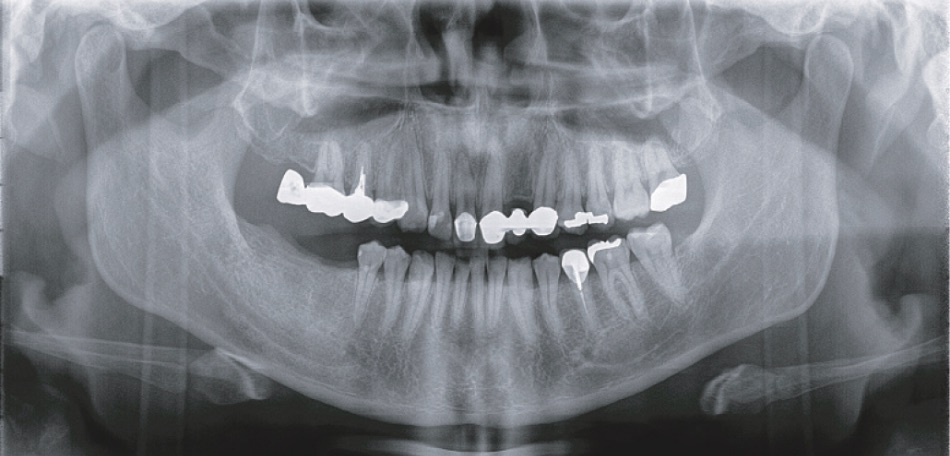

標準パノラマ撮影